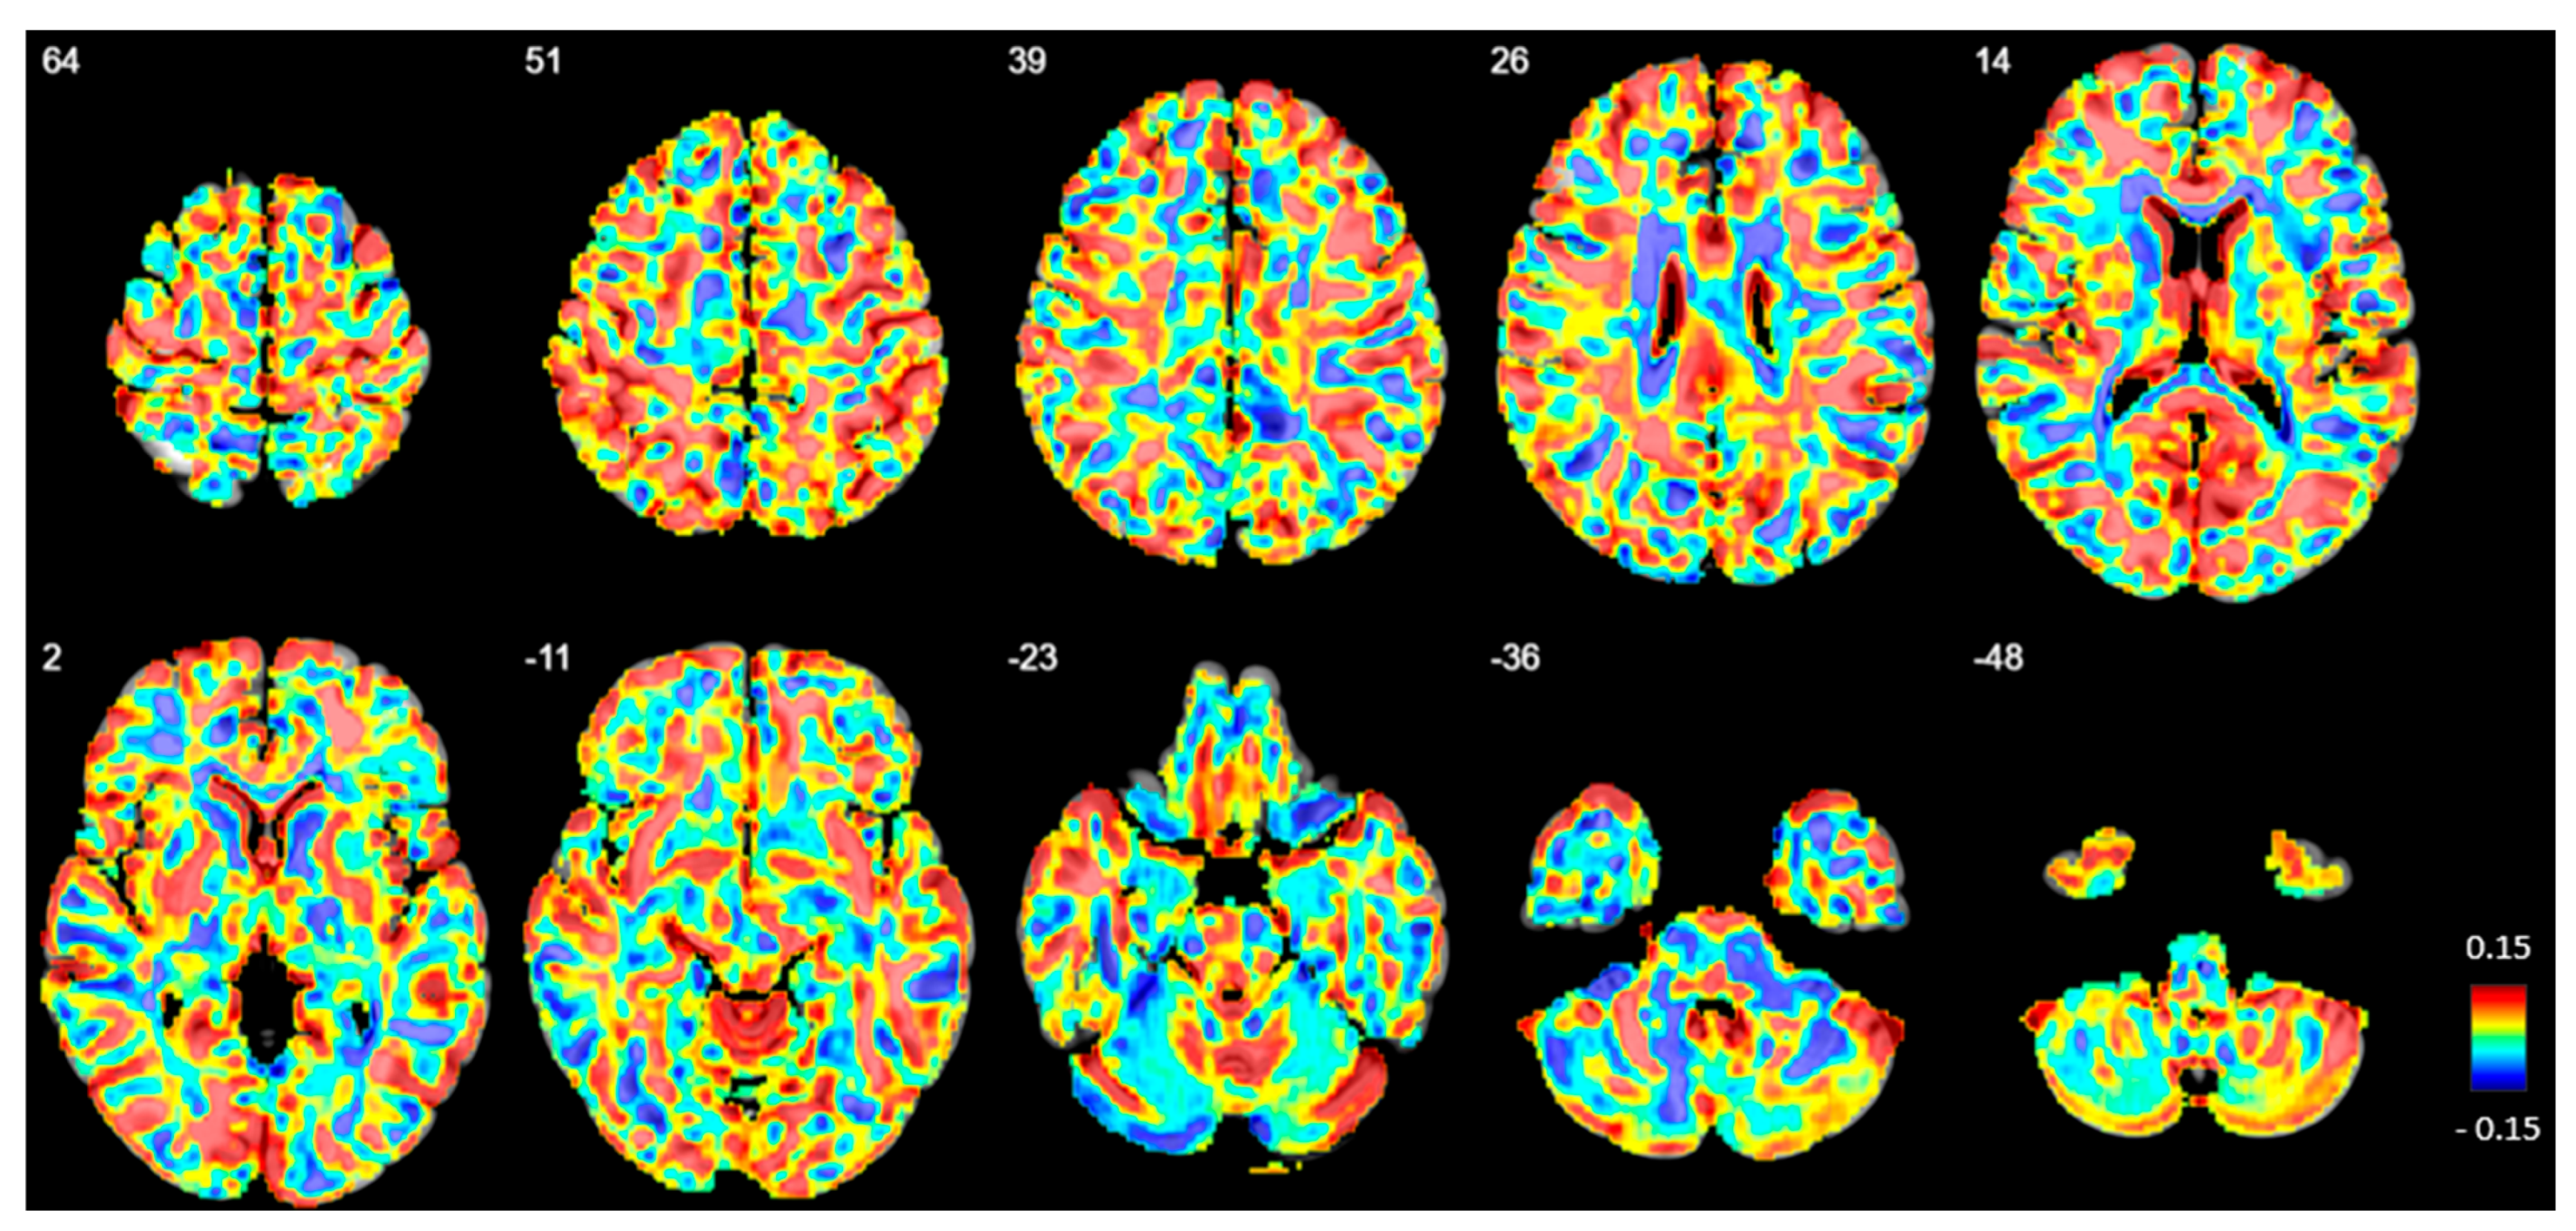

3.3.4. Voxel-Based Group Comparisons